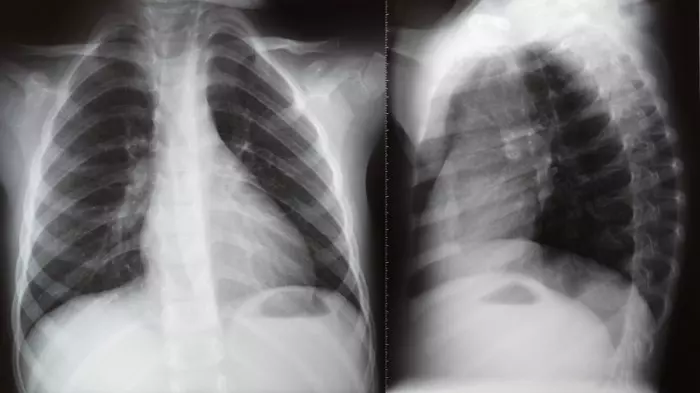

Clinical thesis for lung treatment ‘PNEUMOSTEM’ published in international academic journal

Lung disease stem cell drug designated ‘orphan drug in development stage’

Lung disease stem cell treatment drug ‘PNEUMOSTEM’ application for US clinical trial